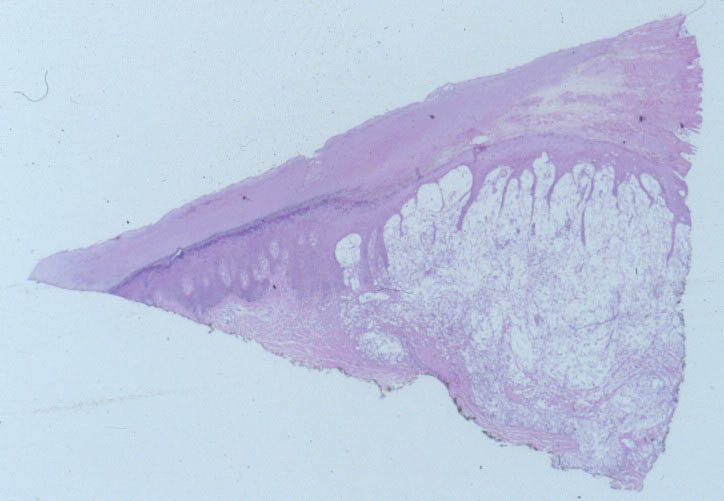

Histologic FindingsIn spinal fluid, urine, and tissue, pathogenic strains of C neoformans grow as round-to-oval yeast, surrounded by a polysaccharide capsule composed of mannose, xylose, and glucuronic acid. The yeast may be single or may have a single budding daughter cell. Cell size varies widely and ranges from 3.5-8 µm in diameter. Rarely, pseudohyphae develop.

India ink, which outlines the organisms by negative contrast, helps to identify the yeast cells in fluids or macerated tissue samples. In fixed tissue, the capsule of C neoformans may also be stained with mucicarmine, which preferentially stains mucopolysaccharides. Tissue sections can be stained with the Fontana-Masson stain to detect melanin precursors in the yeast cell wall. The presence of melanin or melanin precursors is useful in differentiating C neoformans from other yeasts. |